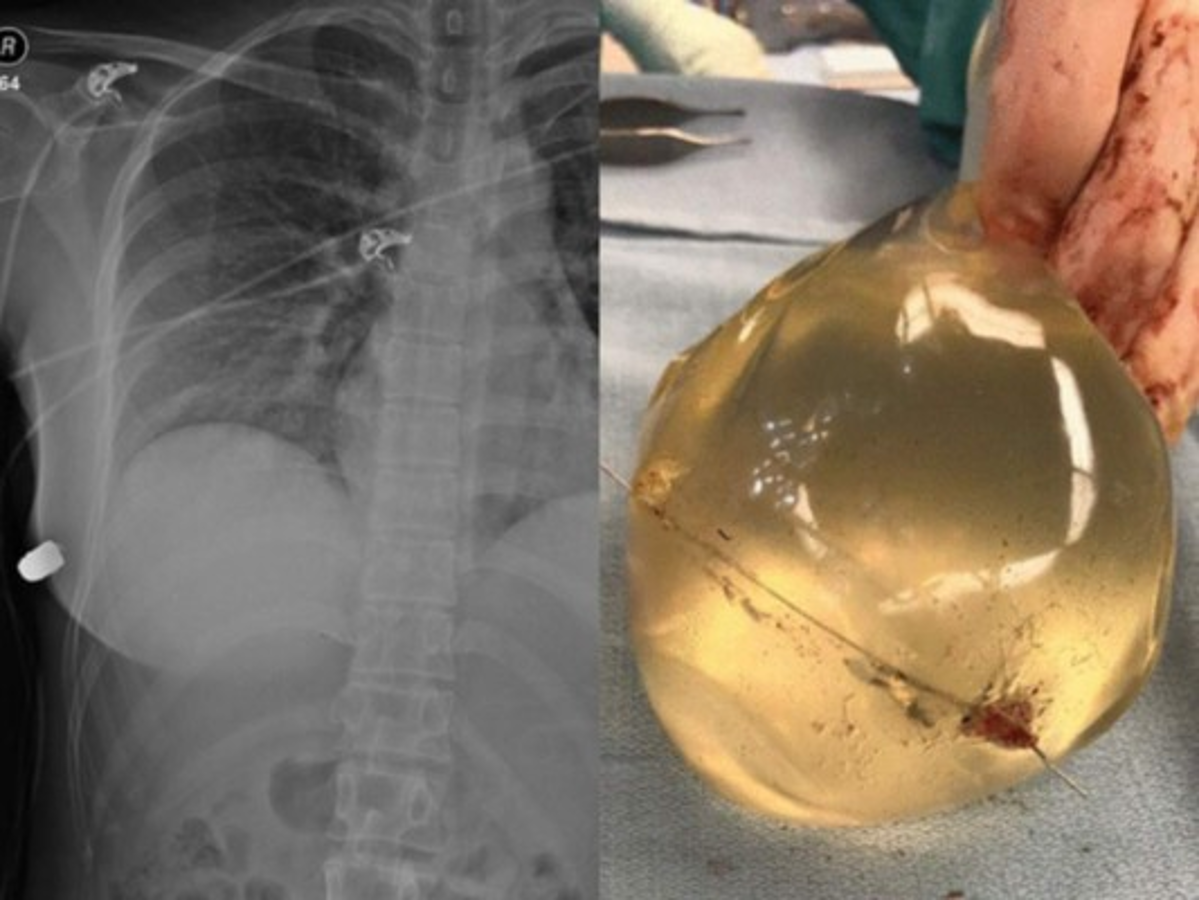

“La entrada de la herida de bala estaba en el seno izquierdo, pero la fractura de costilla estaba en el lado derecho. La bala entró primero en la piel del lado izquierdo, y luego rebotó a través del esternón hacia el seno derecho y le rompió la costilla en el lado derecho”, explicó el galeno.

Los médicos encontraron un objeto duro en la pared torácica anterior inferior derecha de la mujer debajo del seno derecho y luego descubrieron que se trataba de una bala.

Usando radiografías de trauma lograron confirmar que era una bala.